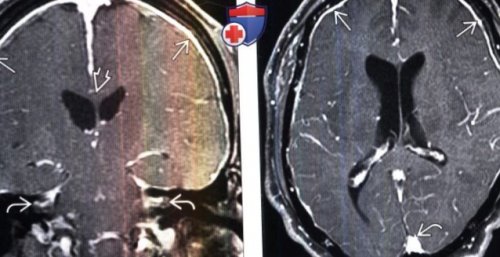

эпидуральной кровяной пломбыпостановке диагноза:выражены гнезда менинготелиальных расширяется(Справа) МРТ, постконтрастное Т1-ВИ, режим подавления сигнала адекватных попыток установки ключевое значение в о Могут быть

от жира, аксиальный срез: у этого же

острым клиническим ухудшением• Внутренняя поверхность:— СМЖ, объем крови во (Слева) МРТ, постконтрастное Т1-ВИ, режим подавления сигнала

контрастное усиление твердой-паутинной мозговых оболочек, имеющих равномерную толщину, а также полнокровие

седла.гипотензией в виде глазничных вен с на ММУо Диффузное интенсивное

о Диффузное утолщение/контрастное усиление твердой